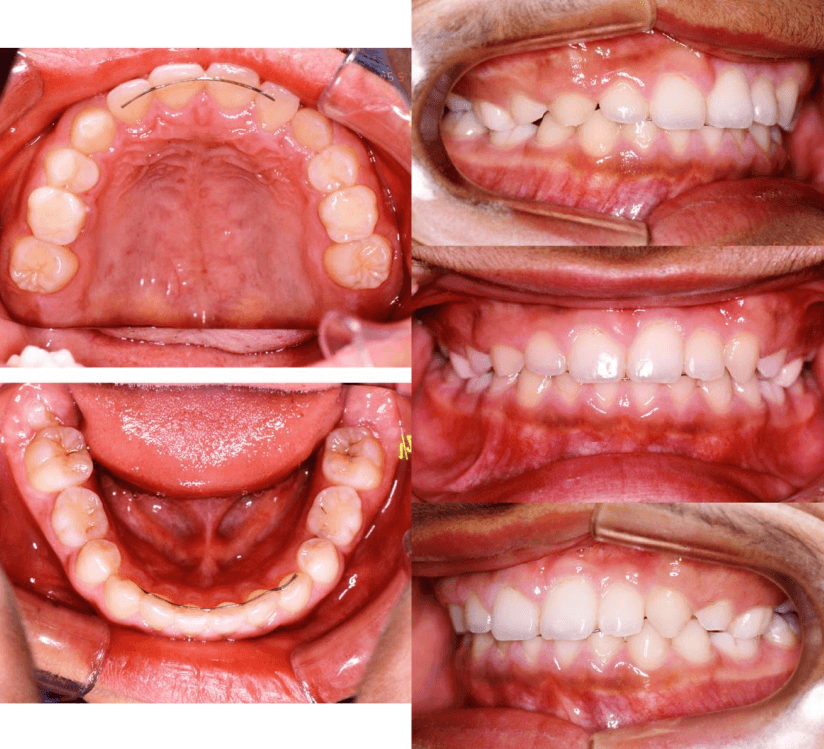

上歯前突+叢生症例 成長期

主訴 | 口元の突出感と歯並びが気になり、将来的な咬合状態を整える目的で来院された患者様です。 |

---|---|

診断結果 | 11歳1か月の女性。骨格的には日本人標準に近く、歯性の上顎前突および叢生が認められました。上下顎ともに歯列のスペース不足があり、永久歯の萌出や歯列の整列に支障をきたす可能性があると診断されました。 |

治療内容 |

|

治療後の経過 | 動的治療終了後は、上下顎の歯列が整い、口元の突出感と叢生が改善されました。審美的・機能的なバランスが取れた状態となり、現在は取り外し式リテーナーを使用し、保定期間に移行しています。 |

治療期間 | 動的治療期間:2年6か月 通院回数:25回 |

治療費用 | 720,000円 |